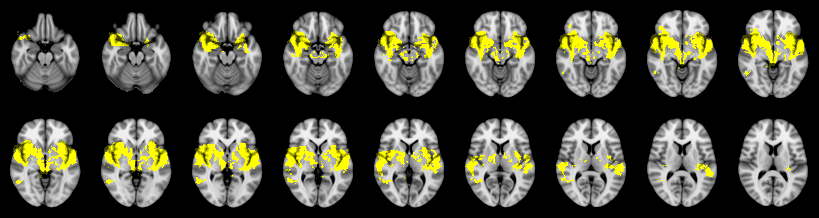

Combined

Tippett:

Fisher:

Stouffer:

Edgington:

Mudholkar–George: